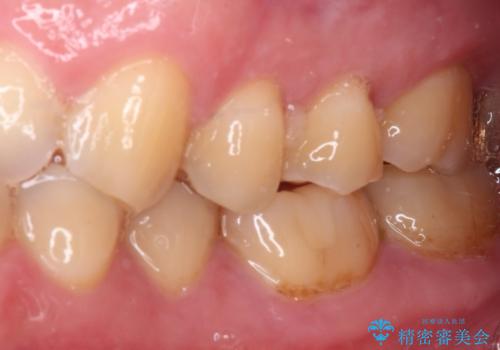

- 左右下顎の奥歯に違和感を感じるとのことで来院された患者様です。

最近ものが挟まりやすくなったり、冷たいものがしみるようになったりと言った症状があり、診査したところ、歯質の欠損や不適修復物などが認められました。

精度の高いセラミックインレーによる修復治療が第一選択となりますが、一方の歯は元々修復物が大きく、咬合力の強い方であったので、セラミッククラウンによる補綴治療を行うこととしました。